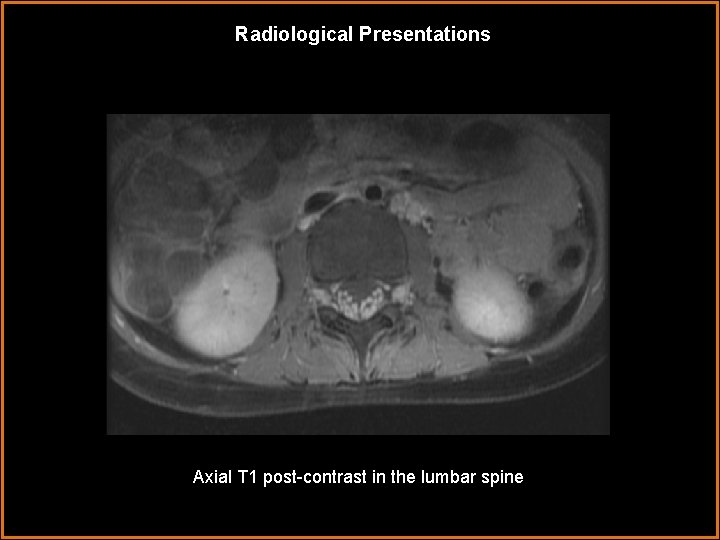

Radiological Presentations Axial T 1 post-contrast in the lumbar spine

Findings and Differentials Findings: The dorsal and ventral nerve roots are enhancing throughout the cervical, thoracic, and lumbar spine. There is avid contrast enhancement and thickening of the cauda equina nerve roots, both in their intrathecal and extraforaminal segments. The spinal cord is not enhancing. Incidental note Differentials: is made • Guillain-Barré syndrome • Miller-Fisher syndrome • Leptomeningeal carcinomatosis • Spinal meningitis of left lower lobe atelectasis.